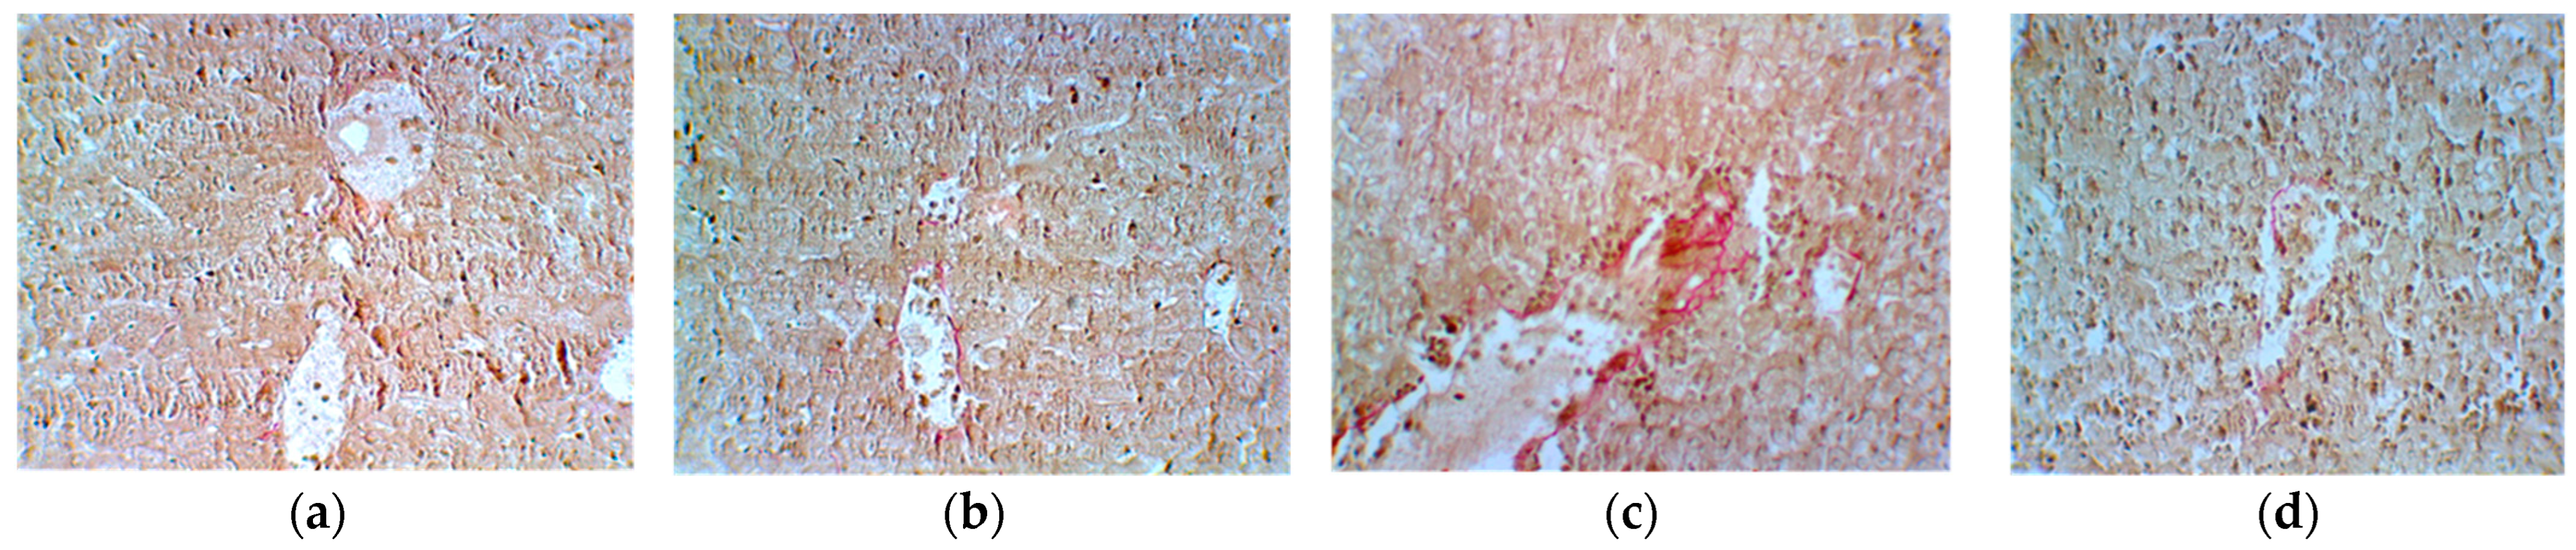

| Group 1 Ascites | Group 2 Ascites + Cyclophosphamide | Group 3 Cyclophosphamide + E. hirsutum Extract | Group 4 E. hirsutum Extract | |

|---|---|---|---|---|

| Reticulin | 0 | 4+ | 2+ | 1+ |

| Van Gieson | 0 | 0 | 3+ | 1+ |